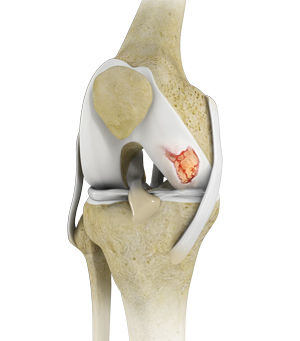

Knee Cartilage Restoration

What is Knee Cartilage Restoration? Knee cartilage restoration is a surgical technique to repair damaged articular cartilage in the knee joint by …